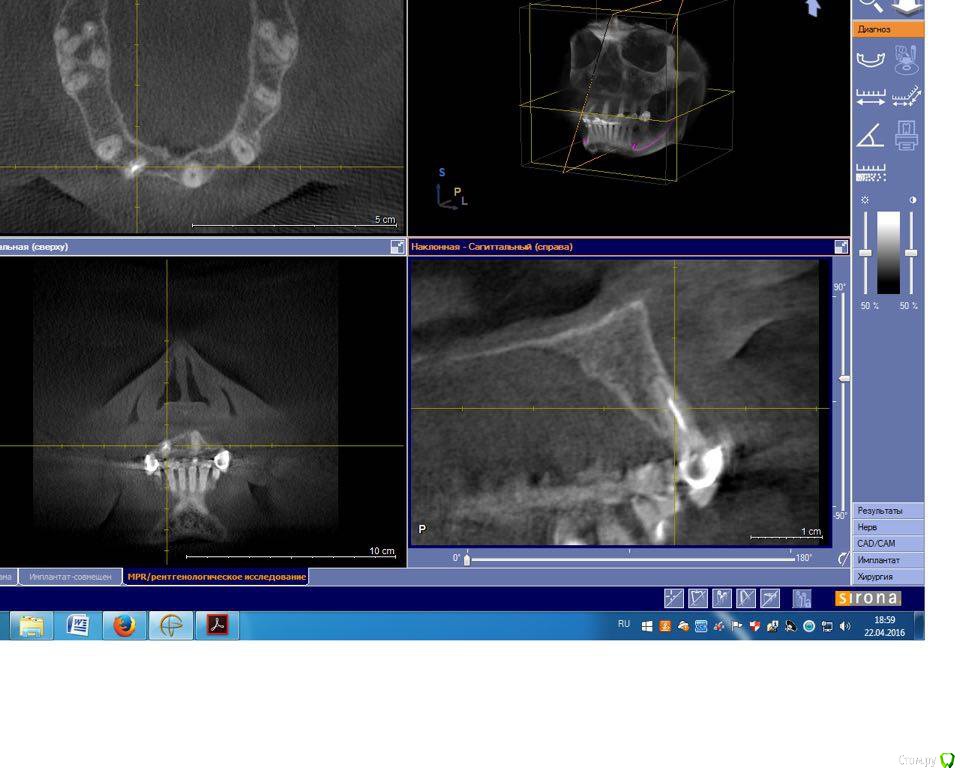

togrul Опубликовано 4 мая, 2016 Поделиться Опубликовано 4 мая, 2016 Добрый день необходим совет по планированию. Планируем удалить зуб 1.2 + одномоментно имплантат Импро 3.6 + ССТ. в области 11 зуба имплантат 3.6 + ССт. у пациента сахарный диабет в районе 8.И 2 вариант НТР в области 11 + имплантация отсрочено. хочу услышать мнение более опытных коллег. буду благодарен. Ссылка на комментарий

pit Опубликовано 6 мая, 2016 Поделиться Опубликовано 6 мая, 2016 Если же говорить только об имплантах, то 1 и консоль будет смотреться лучше. Так как высота сосочка между имплантом и понтиком всегда выше, чем между имплантом и имплантом. Разумеется при правильной моделировке понтика. Но для консольной конструкции я бы предпочел диаметр винта 4,3 и винтовую фиксацию, что в данном случае повлечет за собой приличный объем пластики.Если же линия улыбки закрытая, то 2 импланта. В позицию 12зуба - 3,5, а в позицию 11зуба - 3,0 и минимальный объем пластики. Ссылка на комментарий